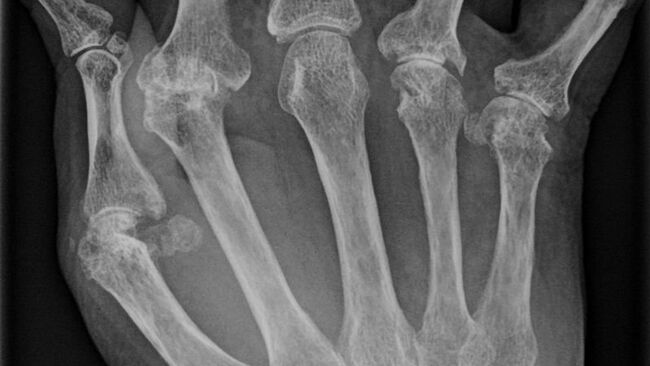

Остеоартроз, ревматоидный артрит и другие хронические болезни, поражающие суставы и мягкие ткани, окружающие кости, возникают или в результате проблем с иммунной системой, ошибочно атакующей соединительные ткани в суставах, или же в результате развития воспалений и травм, ведущих к гибели клеток.

На сегодняшний день, по оценкам ВОЗ, примерно 5% населения Земли страдает от подобных проблем с суставами, и в некоторых странах, таких как США, свыше половины пожилых людей страдает от различных форм ревматизма.